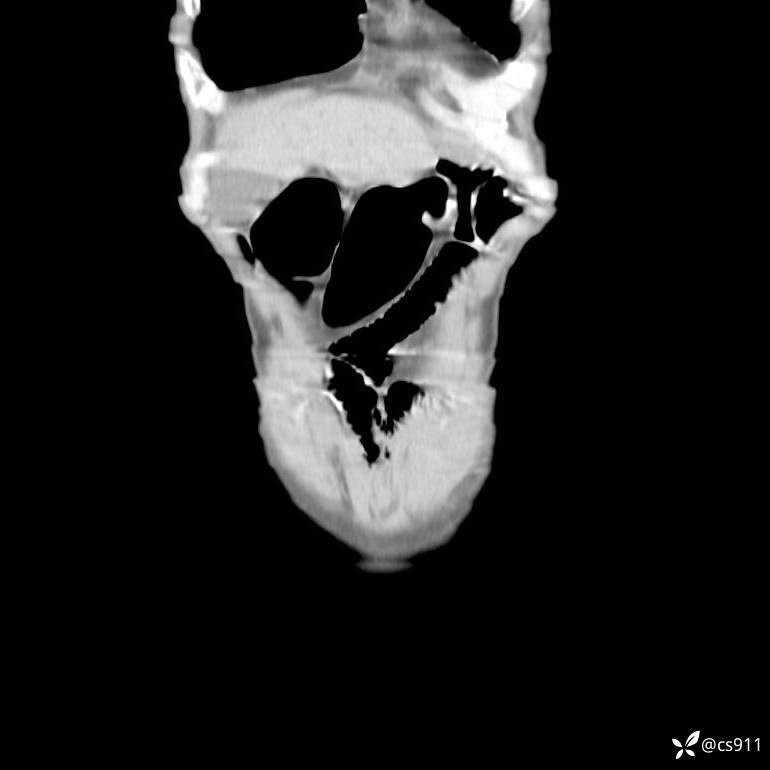

男,77岁,腹痛、腹胀伴恶心呕吐1天。呕吐胃内容物,非喷射性呕吐,有咖啡色样胃内容物,诉有胃穿孔病史。查体:全腹平,下腹部压痛,全腹无反跳痛,叩诊呈浊音,移动性浊音阴性,肠鸣音减弱,1-2次/分。肛检:直肠未扪及明显肿物,可触及大量粪块。

T 36.6℃ P 80次/分 R 26次/分 BP 100/60mmHg

白细胞(WBC) H 14.55 10e9/L 4-10

中性粒细胞百分率(NEUT%) H 85.7 % 40-75

血淀粉酶(AMY) HH 1859 U/L 35-135

癌胚抗原(CEA) H 27.44 ng/ml 0-5